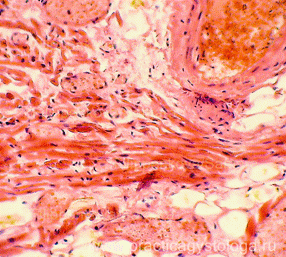

Рис. 1-4. Пучки мышечных волокон истончённых за счёт слабо и умеренно выраженной атрофии. Сочетаются с очаговым периваскулярным липоматозом, очагово-диффузным интрамуральным липоматозом, участками волнообразной деформации мышечных волокон миокарда. Окраска: гематоксилин-эозин. Увеличение х100 и х250.

Таким образом, в изученных микропрепаратах выраженные признаки дистрофии миокарда в виде сочетания групп кардиомиоцитов в состоянии гипертрофии, пучков мышечных волокон в состоянии атрофии, очагов межуточной круглоклеточной инфильтрации, очагового периваскулярного и интрамурального липоматоза.